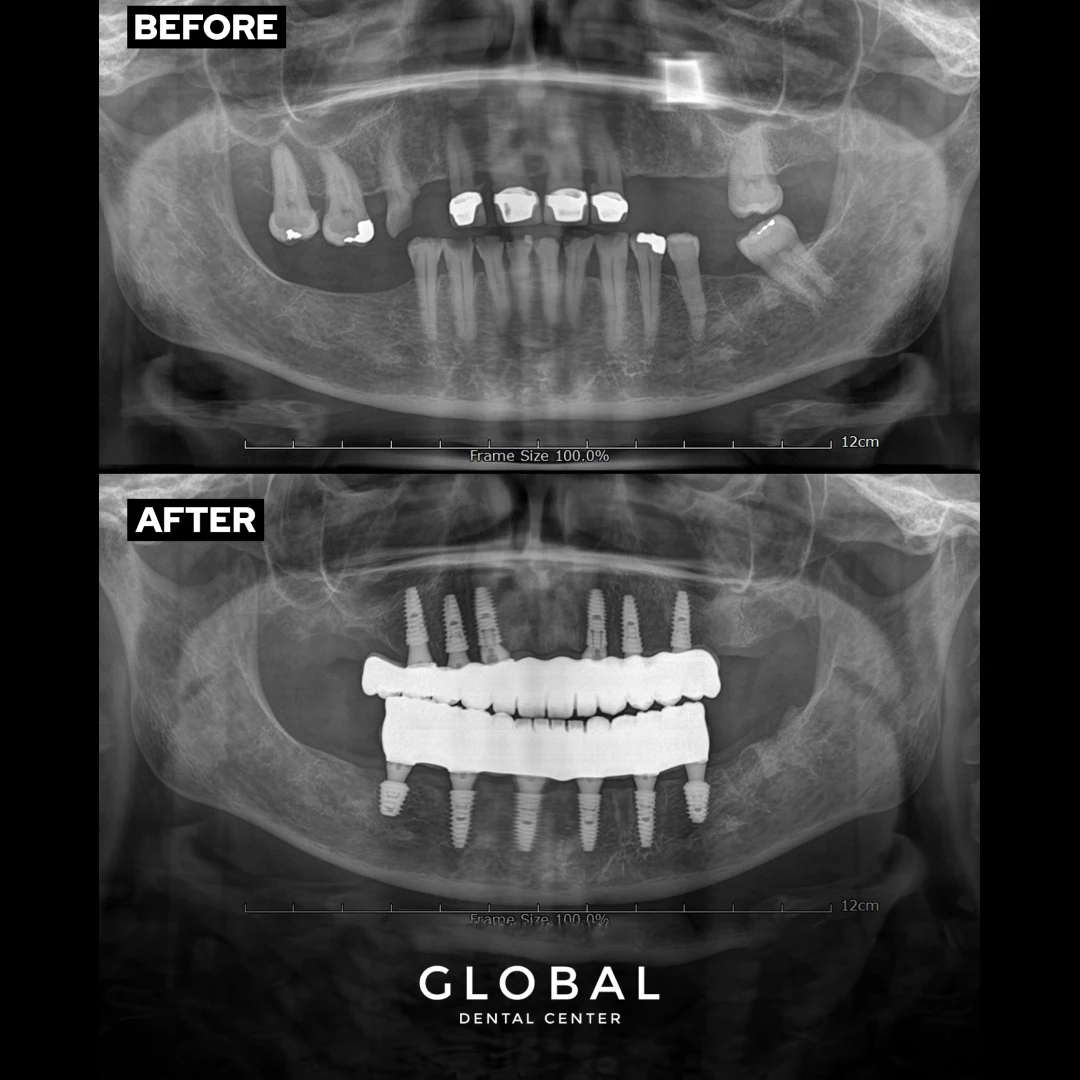

Pour les personnes qui ont perdu la plupart de leurs dents, il existe plusieurs options disponibles pour compléter les restaurations bouche pleine. Les prothèses traditionnelles sont l’option la plus abordable, mais elles n’offrent pas la même stabilité que les dents naturelles et n’arrêtent pas la perte osseuse dans la mâchoire. Par conséquent, la technique All-on-four, qui est l’une des prothèses hybrides implantoportée, est un choix de première classe en termes de fonction et d’apparence. Cette technique extraordinaire est une solution chirurgicale basée sur la mise en place de 4 implants également espacés et à des angles appropriés dans la mâchoire supérieure ou inférieure pour soutenir l’ensemble de la prothèse. Tout-sur-4 élimine généralement la nécessité de toutes, les procédures de greffe osseuse supplémentaires et le soulèvement des sinus. Cette configuration d’implant offre la plus grande stabilité et s’adapte à la prothèse complète, empêchant le mouvement et éliminant le besoin d’adhésifs dentaires salissants.

La différence la plus évidente entre All On 4 et All On 6 est le nombre d’implants ajoutés. Le All On 4 utilise quatre implants, tandis que le All On 6 en utilise six. Cependant, il y a plus de différences à considérer, de sorte que la plupart des cabinets dentaires choisiront l’intervention qu’ils préfèrent en fonction de leur opinion clinique, de leur pratique et du volume osseux du patient.

Au Global Dental Center, nos dentistes et chirurgiens buccaux recommandent généralement l’intervention All On 6 parce que nous croyons qu’elle procure une meilleure force et stabilité, ce qui se traduit par un sourire plus confortable et plus durable. Il est important que chaque fois que vous mâchez ou mordez quelque chose, la pression soit répartie uniformément sur vos implants et votre mâchoire. Nous croyons que l’emplacement et le placement de ces deux implants supplémentaires procurent une solidité, une stabilité et des avantages à long terme.

Ces implants supplémentaires fournissent non seulement plus de soutien pour votre morsure, mais aussi plus de force pour votre mâchoire. Tu savais que sans dents, ta mâchoire commence à se détériorer ? Pour cette raison, les personnes qui portent un dentier depuis longtemps semblent habituellement plus âgées et leurs mâchoires semblent enfoncées lorsqu’elles retirent leur dentier. Cela ne se produit pas avec les implants dentaires parce que l’implant stimule la mâchoire et l’aide à rester forte. L’approche All on 6 procure une stimulation et une force supplémentaires à votre mâchoire.